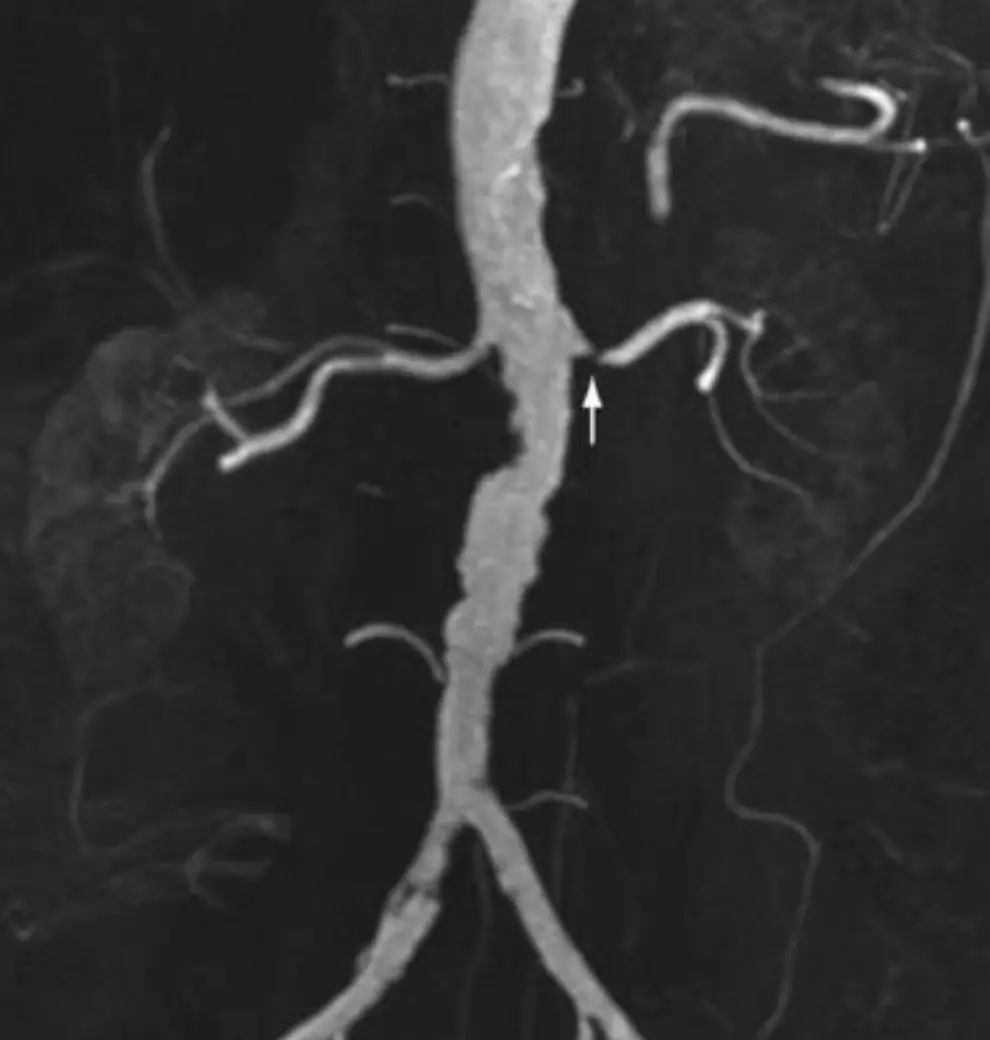

圖片為腹部磁振血管造影(MR angiography,MRA),採最大強度投影(maximum intensity projection, MIP)重建,以冠狀面(coronal)呈現腹主動脈及雙側腎動脈全貌。

- 腹主動脈管壁不規則,呈現動脈粥狀硬化(atherosclerosis)典型的管腔不均勻表現。

- 白箭頭(↑)指向左側腎動脈開口處(ostium),可見明顯局部管腔狹窄,血管訊號中斷,符合血管動脈硬化斑塊(atherosclerotic plaque)侵犯腎動脈起源處。

- 右側腎動脈相對通暢,但主動脈壁亦可見動脈硬化改變。

- 整體表現與臨床情境(72 歲、高血壓、高血脂、左腎比右腎小 2 cm)高度吻合,為動脈硬化性腎動脈狹窄的典型影像。

臨床意義: MRA 是非侵入性診斷腎動脈狹窄最準確的工具,敏感度達 96.6%(針對 ≥50% 狹窄),優於都卜勒超音波(84%)及 capto